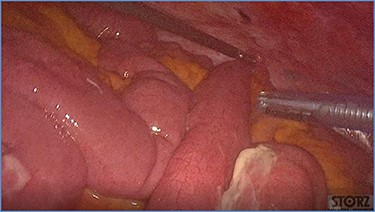

fluid collection in the peritoneal cavity. Subsequent CT confirmed the presence of diffuse fluid collection in the peritoneal cavity (Fig. 1) but no free air, with distention, bundling and thickening of some small bowel in the left quadrant (Fig. 2). The patient was therefore admitted for supporting therapy (intravenous fluids and antibiotics) with the suspicion of cocaine-induced small bowel ischemia. Twelve hours later, signs and symptoms of diffuse peritonitis developed: worsening diffuse abdominal pain with rebound guarding at examination, a significant increase in WBCs count (16.15 × 103/μl) and neutrophilia (88%), lengthening of coagulation times (INR: 1.68; aPTT: 33.0 s) and increase in fibrinogen (430 mg/dl) and D-Dimer (2275 ng/ml). Therefore, urgent surgical exploration of the abdomen through a three-port open laparoscopic approach was performed, confirming the presence of 1200 ml of exudative fluid and fibrin clots (Fig. 3). Several adhesions between greater omentum, abdominal wall and small bowel underwent blunt dissection. Thorough exploration of the small bowel revealed two ischemic segments located at about 50 and 100 cm from the Treitz ligament (Fig. 4). The large bowel appeared normal. The existence of non-visible gastro-duodenal perforations was ruled out with the administration of 500 ml of saline with 20 ml of methylene blue through the nasogastric tube. An iv bolus of sodium heparin, 10 000 IU, was then administered, performing a 30-min peritoneal lavage with 5 l of saline solution at 37°C. After reaspiration of peritoneal lavage, a new complete exploration of the small bowel was performed, showing complete revascularization of the two ischemic small bowel segments (Fig. 5). Two tubular drainage tubes were placed in the left and right colic gutters. Culture examination of peritoneal exudate was positive for multi-sensitive Escherichia coli and Enterococcus, thus confirming bacterial translocation peritonitis. Postoperative therapy included the administration of iv piperacillin–tazobactam and subcutaneous low molecular weight heparin. Postoperative recovery was smooth, with oral feeding on the second postoperative day (POD), drainage removal on POD 3, complete bowel function restored on POD 4 and home discharge on POD 5. At 15- and 30-day-follow-up, the patient showed full recovery, being now followed by a specialized support structure for his drug abuse.

Progressive small bowel revascularization perceived by slow reappearance of vasa recta after peritoneal lavage.